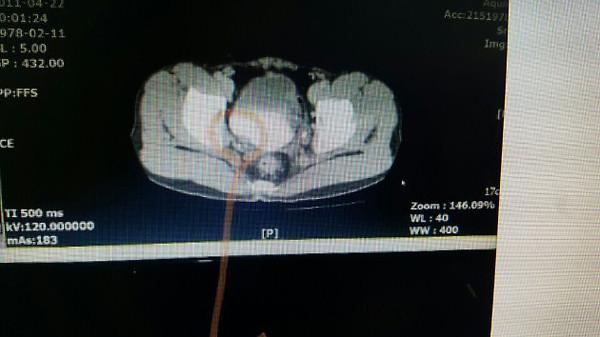

위사진은 암으로 추측되는부분이라도 개인병원 의사가 찾아주신 자료 중 하나입니다.

이게 맞을까요? 첫번째  2011년, 그다음 2015년 세번째도 2011년 그다음 2016년입니다. ....

올려주신 영상은 PELVIS 쪽의 조영증강(ENHANCED) CT 검사네요.

첫째, 셋째 사진이 2011(초진검사) 하신 영상이고,

둘째 ,넷째 사진이 15,16년 사진이시죠.

사진이 명확치 않아 확인지 조금 어렵지만

사진상에 보이는 것은 네번째 마지막 사진에만 확실한 종양의심부분이 관찰이 되고 있습니다.

추가질문  「 좀 더 선명한 사진인데....다시한번 봐주시겠습니까..... 」 에 대한 답변입니다.

아. 정확히 보이시네요.

첫번째 사진 2011년 4월22일 ENHANCE CT 영상에서도

동그라미 쳐진 부분(화살표) 부분이 조영증강된 것이 확인이 됩니다.

나머지도 보시기 쉽게 동그라미 표시를 해드렸습니다.